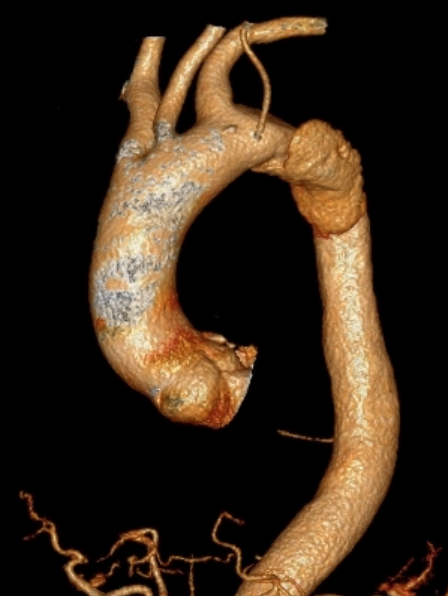

我院对新技术开展格外重视,全力支持新技术的开展。在易俊方主任的精心组织下,术前经过反复、严谨、精确的测量,积极做好术前准备,与患者充分沟通并取得患者的信任与配合。8月3号,我院介入血管外科在急诊科、急重症医学科、麻醉科、介入导管室等多科室协作下,经过3个小时的努力,手术进行顺利,术后造影效果满意。

8月3号,晋江市医院介入血管外科在急诊科、急重症医学科、麻醉科、介入导管室等多科室协作下,成功完成福建省县级市医院首例自主完成的“胸主动脉夹层腔内支架隔绝+体外开窗左锁骨下动脉分支支架植入”手术,有效防止主动脉夹层血管破裂致命性出血,为血管疾病患者保驾护航,标志着我院介入血管外科在大动脉疾病的腔内治疗方面踏上新的起点。

7月30号,复查主动脉CTA,显示“主动脉夹层(Debakey III型)伴部分腔内血栓形成大致同前,不排除伴壁间血肿”。经介入血管外科组内讨论,易俊方主任考虑到患者夹层有效保守治疗后未再进展,急性期平稳渡过,决定在发病第10天为患者行“DSA下胸主动脉腔内支架隔绝术+左锁骨下动脉开窗支架植入术”。